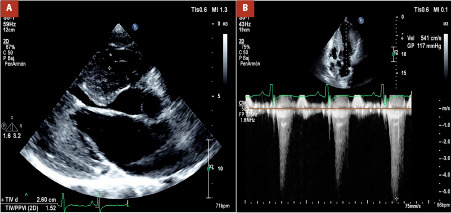

Hypertrophic cardiomyopathy has a different presentation spectrum, including left ventricular outflow tract obstruction. The most common phenotype is the asymmetric septal variant, with the mid-apical variant being rare. On the other hand, there are specific mutations associated with hypertrophic cardiomyopathy, with the Filamin C variant being an unusual condition in these patients. Therefore, we present the case of a 23-year-old male patient with a diagnosis of hypertrophic cardiomyopathy in whom a Filamin C variant was documented. Given the inadequate response and persistence of symptoms to medical management, a myectomy procedure was performed with a transapical approach, with subsequent improvement in clinical symptoms and outflow tract obstruction. This case illustrates a rare variant with a surgical approach different from the conventional transaortic approach, with marked improvement in symptoms.